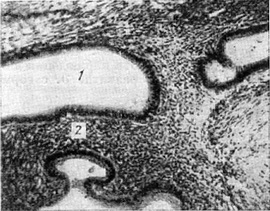

![]() Внутрішній ендометріоз матки: 1 - кістозно розтягнута залоза; 2 - цитогенная строма. |

Патологічна анатомія. При дифузному внутрішньому ендометріозі матки стінка її потовщена (до 4-5 см), при осередковому ураженні виявляються великі і дрібні вузли, які не мають чітких меж з навколишньою тканиною стінки матки; на розрізі тканина пористого будови. В товщі її знаходяться залізисті освіти (рис.), оточені цитогенной стромою (гетеротопический ендометрій). Залози різної форми і величини, іноді різко розширені. Рідко в міометрії спостерігаються кісти. Залози і кісти вистелені однорядним циліндричним епітелієм, іноді сплюснутим. Залежно від глибини проникнення гетеротопического ендометрію в міометрій розрізняють ендометріоз матки I ступеня - проникнення залоз і строми з базального шару ендометрію не більше ніж на одне поле зору, II ступеня - до 1/2 товщини стінки матки і III ступеня - до серозного покриву. При II і III ступеня ендометріоз матки відзначається і гіперплазія м'язових волокон (звідси і назва аденоміоз). Гистофизиологическая реакція в гетеротопическом ендометрії в лютеїнову фазу циклу спостерігається рідко. Найбільш часто гетеротопический ендометрій реагує на естрогени. Е. шийки матки зустрічається рідше.